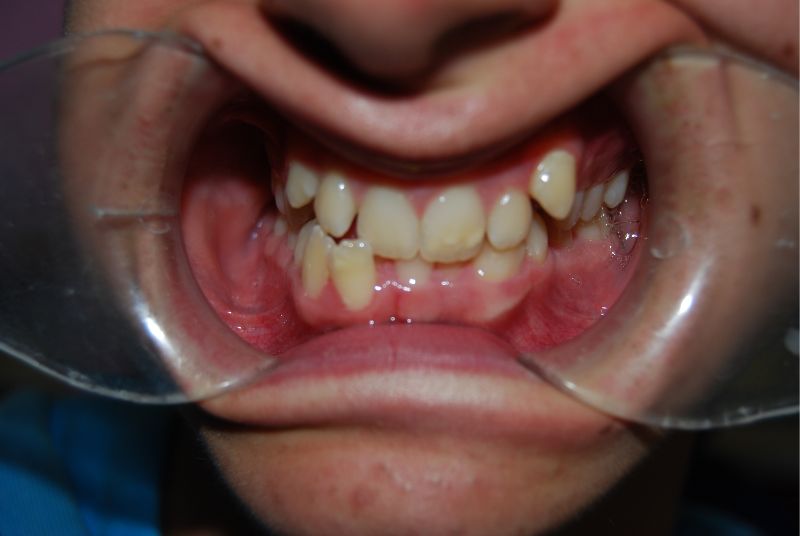

apiñamiento dental

El apiñamiento dental o la aparición de dientes torcidos es una maloclusión debida a una falta de espacio en uno o ambos maxilares. En estos casos, las piezas dentales no tienen la posición correcta y se apiñan o se tuercen. Por ello, es importante corregirlo mediante ortodoncia durante los primeros años de vida.

El apiñamiento dental es una maloclusión debida a una falta de espacio en uno o ambos maxilares para todos los dientes presentes en boca. Por ello, no se ven alineados, sino torcidos o desalineados. Existen dos tipos de apiñamiento dental:

dientes torcidos